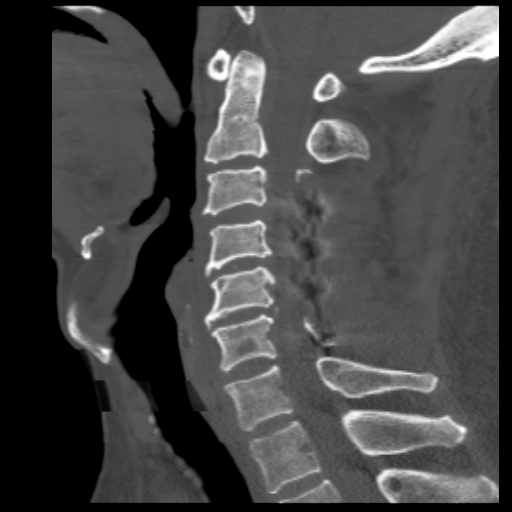

术前脊髓造影后CT,明显可见脊髓压迫